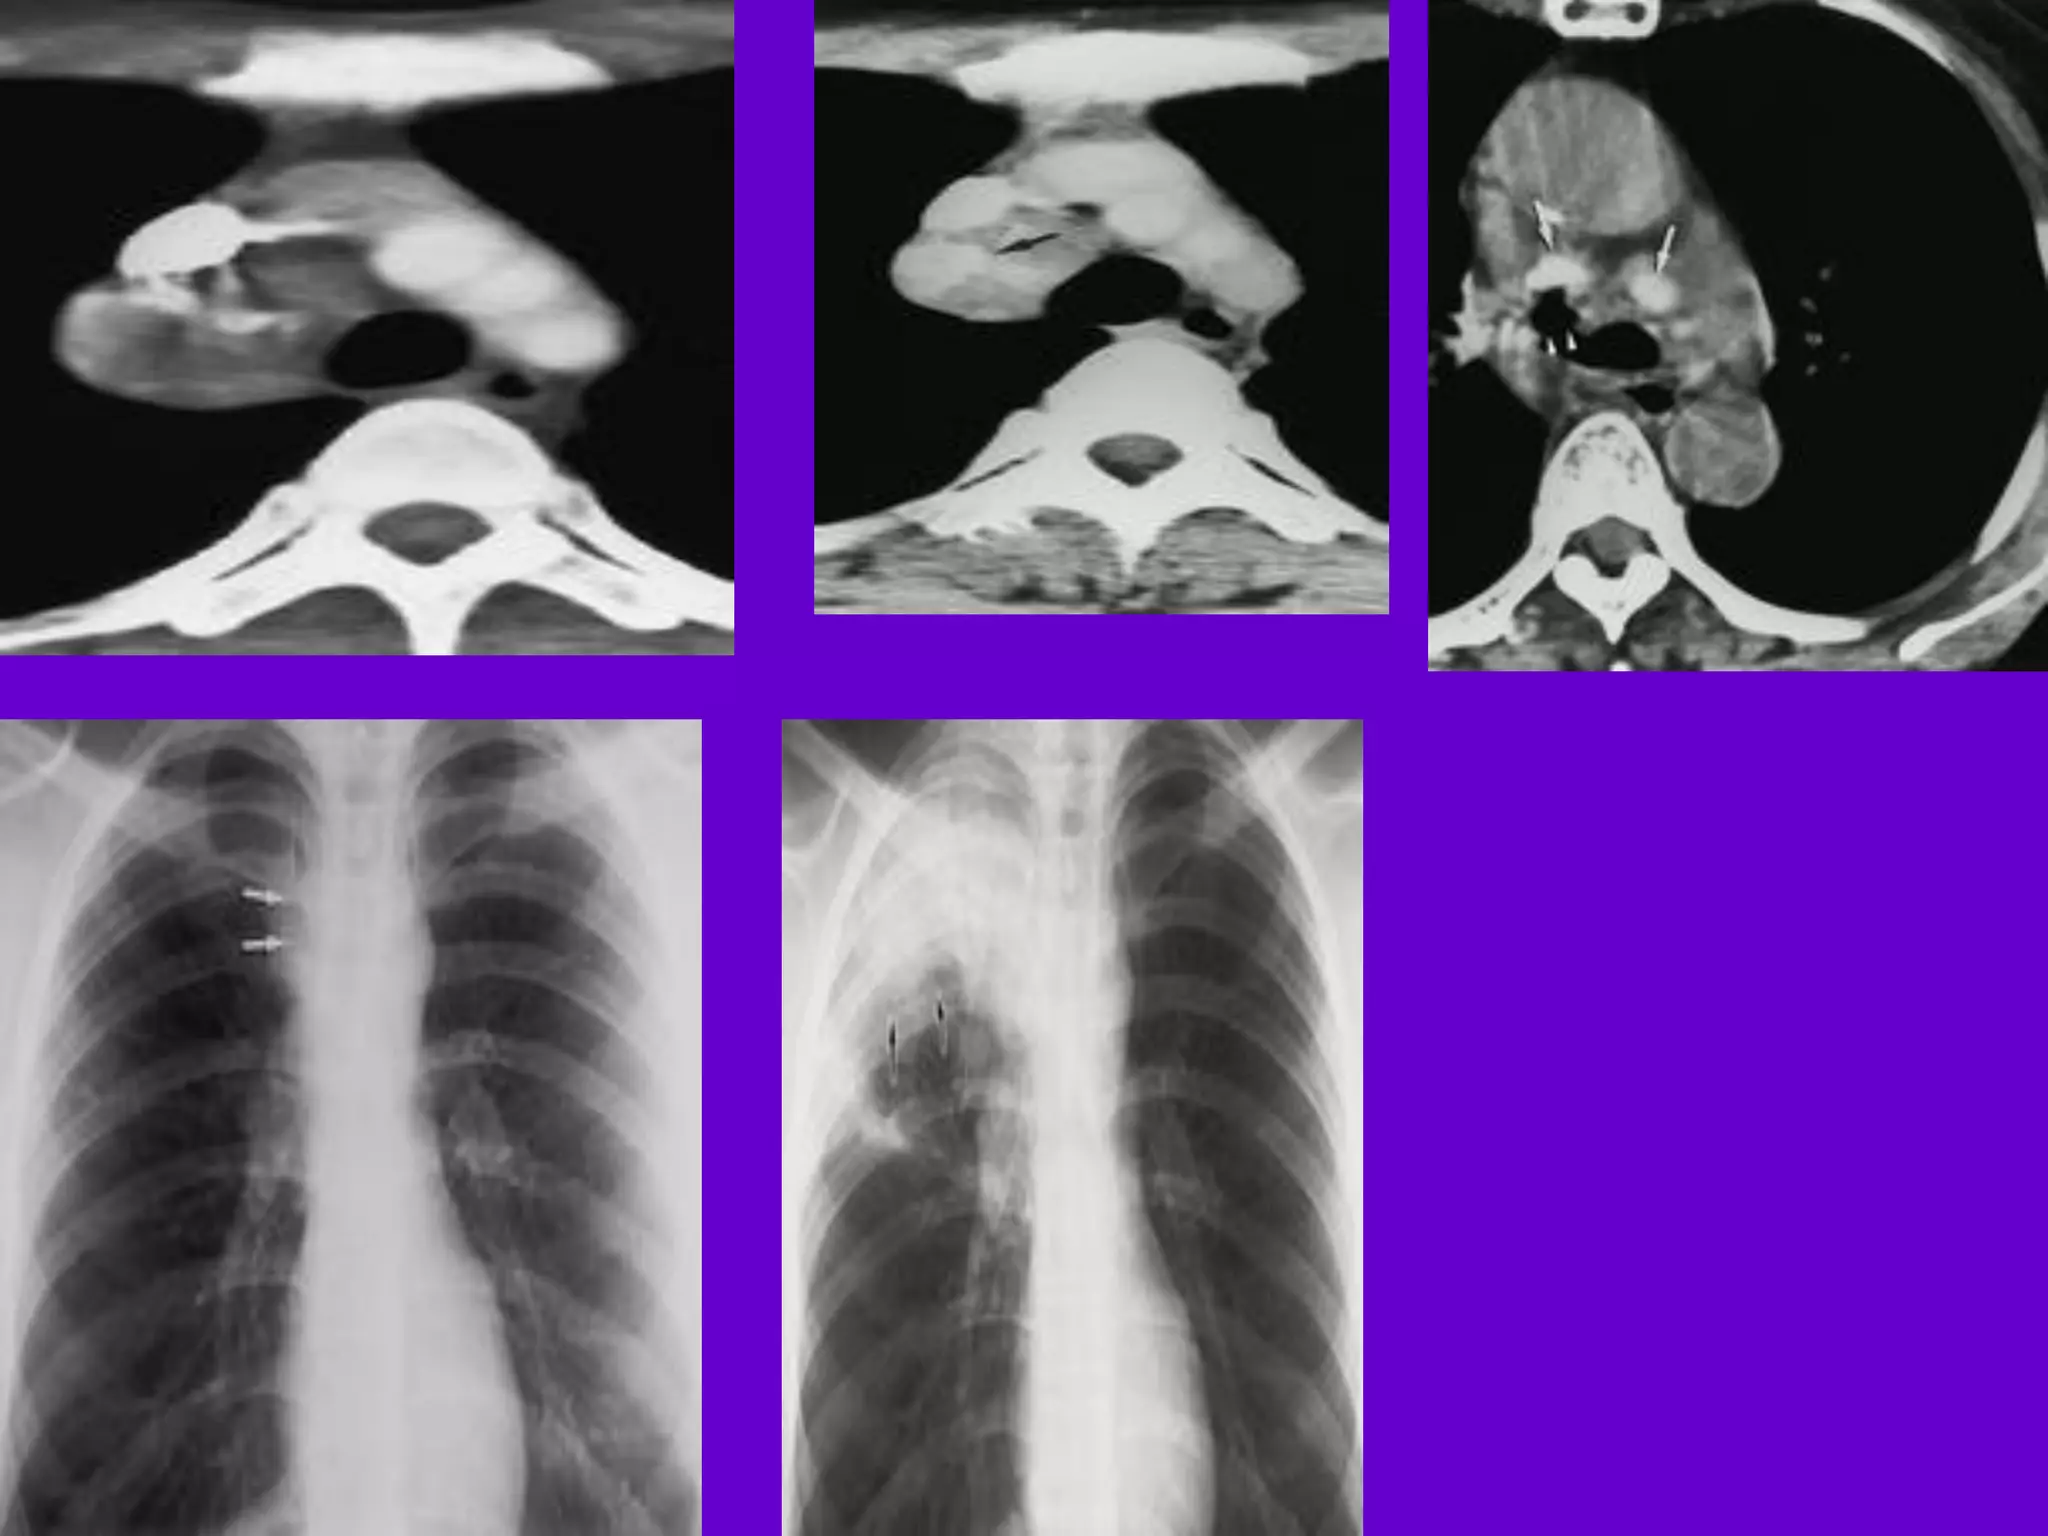

CT Scan and MRI Scan in the

diagnosis of TB

􀂄 The advent of CT and MRI imaging in

the last two

decades has redefined the approach in

analysis of

various diseases including TB.*

􀂄 CT and MRI have shown several

advantages over

conventional radiology in early diagnosis

and follow-up

of TB in different parts of the body.

*Buxi TBS Indian J Pediatr 2002;69:965-972

Hilar and Mediastinal

Lymphadenopathy

CT and MRI depict the hilar and

mediastinal LN

equally well.

􀂄 Calcification in the nodes is however

better seen on

CT.

􀂄 Necrosis is seen as focal areas of low

attenuation on

a CECT.

􀂄 On MRI focal necrosis is seen as areas

of increased

signal intensity on T2W images.

􀂄